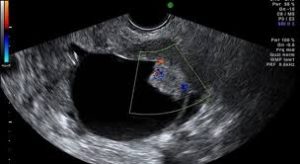

L’ecografia transvaginale è il primo strumento utilizzato nella conferma di un sospetto diagnostico della presenza di una massa pelvica alla visita ginecologica. Essa può dare ottimi risultati ed ha una sensibilità che può arrivare al 90%.

Quando si evidenzia, con la visita ginecologica oppure con l’ecografia una massa ovarica, è fondamentale eseguire una ecografia transvaginale specifica al fine di classificarla come più probabilmente benigna o più probabilmente maligna per poter decidere il successivo programma assistenziale.

Avendo conseguito la certificazione IOTA, nel nostro studio si è scelto di utilizzare i criteri dell’ International Ovarian Tumor Analysis che sono ampiamente validati nella pratica clinica da molti studi internazionali e che ci consentono di confermare il sospetto clinico e di classificare la massa come benigna, borderline o maligna, utilizzando i parametri della classificazione e gli indici ad essa connessi.